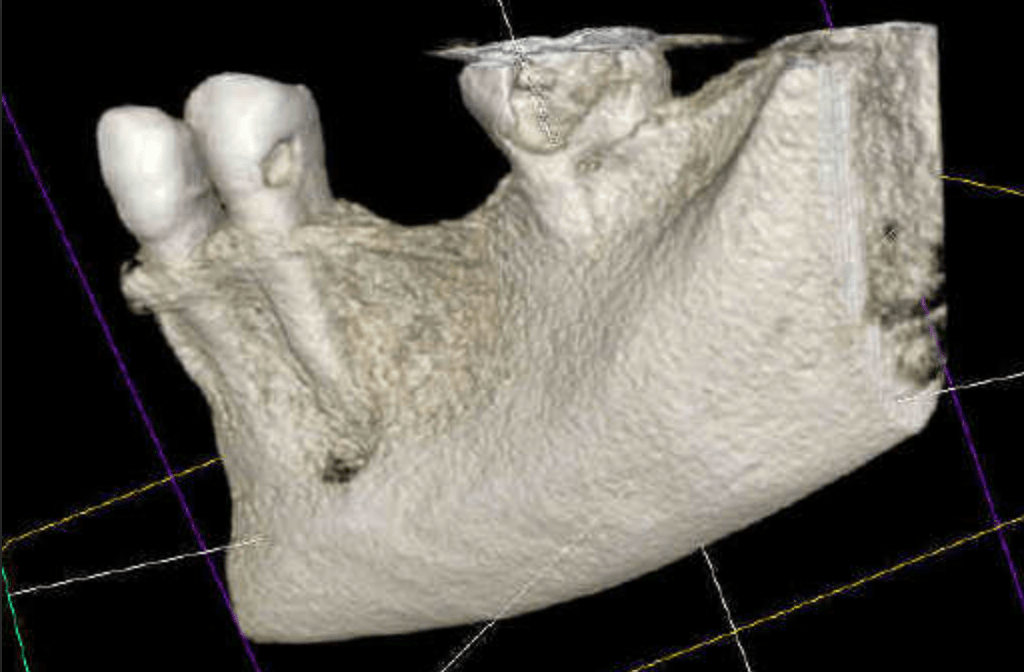

Vertical root fracture